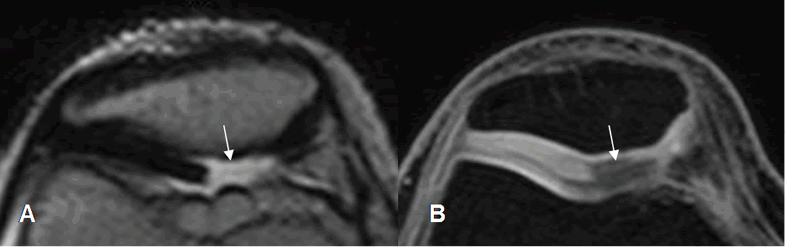

Fig 166. Condromalacia patelar grado 2.

A: RM axial en T2 y B: RM axial en 3D T1 STIR. Erosión del cartílago articular a nivel del vértice, menor del 50%.

Fig 167. Condromalacia patelar grado 2.

A y B: RM axial en 3D T1 STIR. Adelgazamiento del cartílago articular menor del 50%.